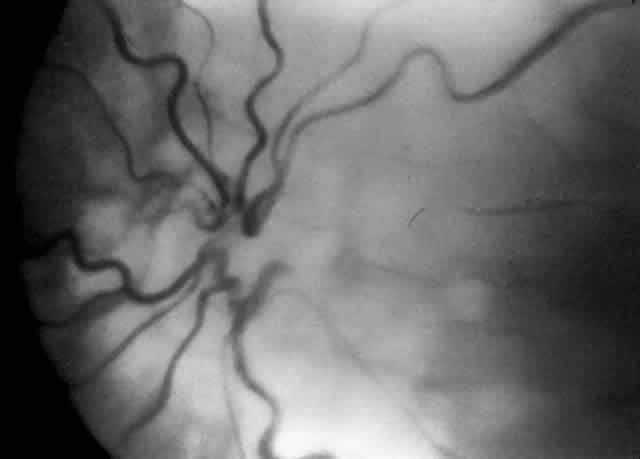

ROP accounts for a large number of retinal detachments in the pediatric population. The International Classification of Retinopathy of Prematurity helped greatly to improve communication about, and consequently treatment of, ROP. It describes affected eyes in terms of stage, zone, and absence or presence of plus disease18 (Figs. 1, 2, and 3). Screening of premature infants is an important feature in the care of ROP, which is perhaps the most significant and enduring finding of the Cryotherapy for Retinopathy of Prematurity Study (Cryo-ROP Study).19

Fig. 3. Dilated and tortuous vessels in the posterior pole, which by definition is plus disease.